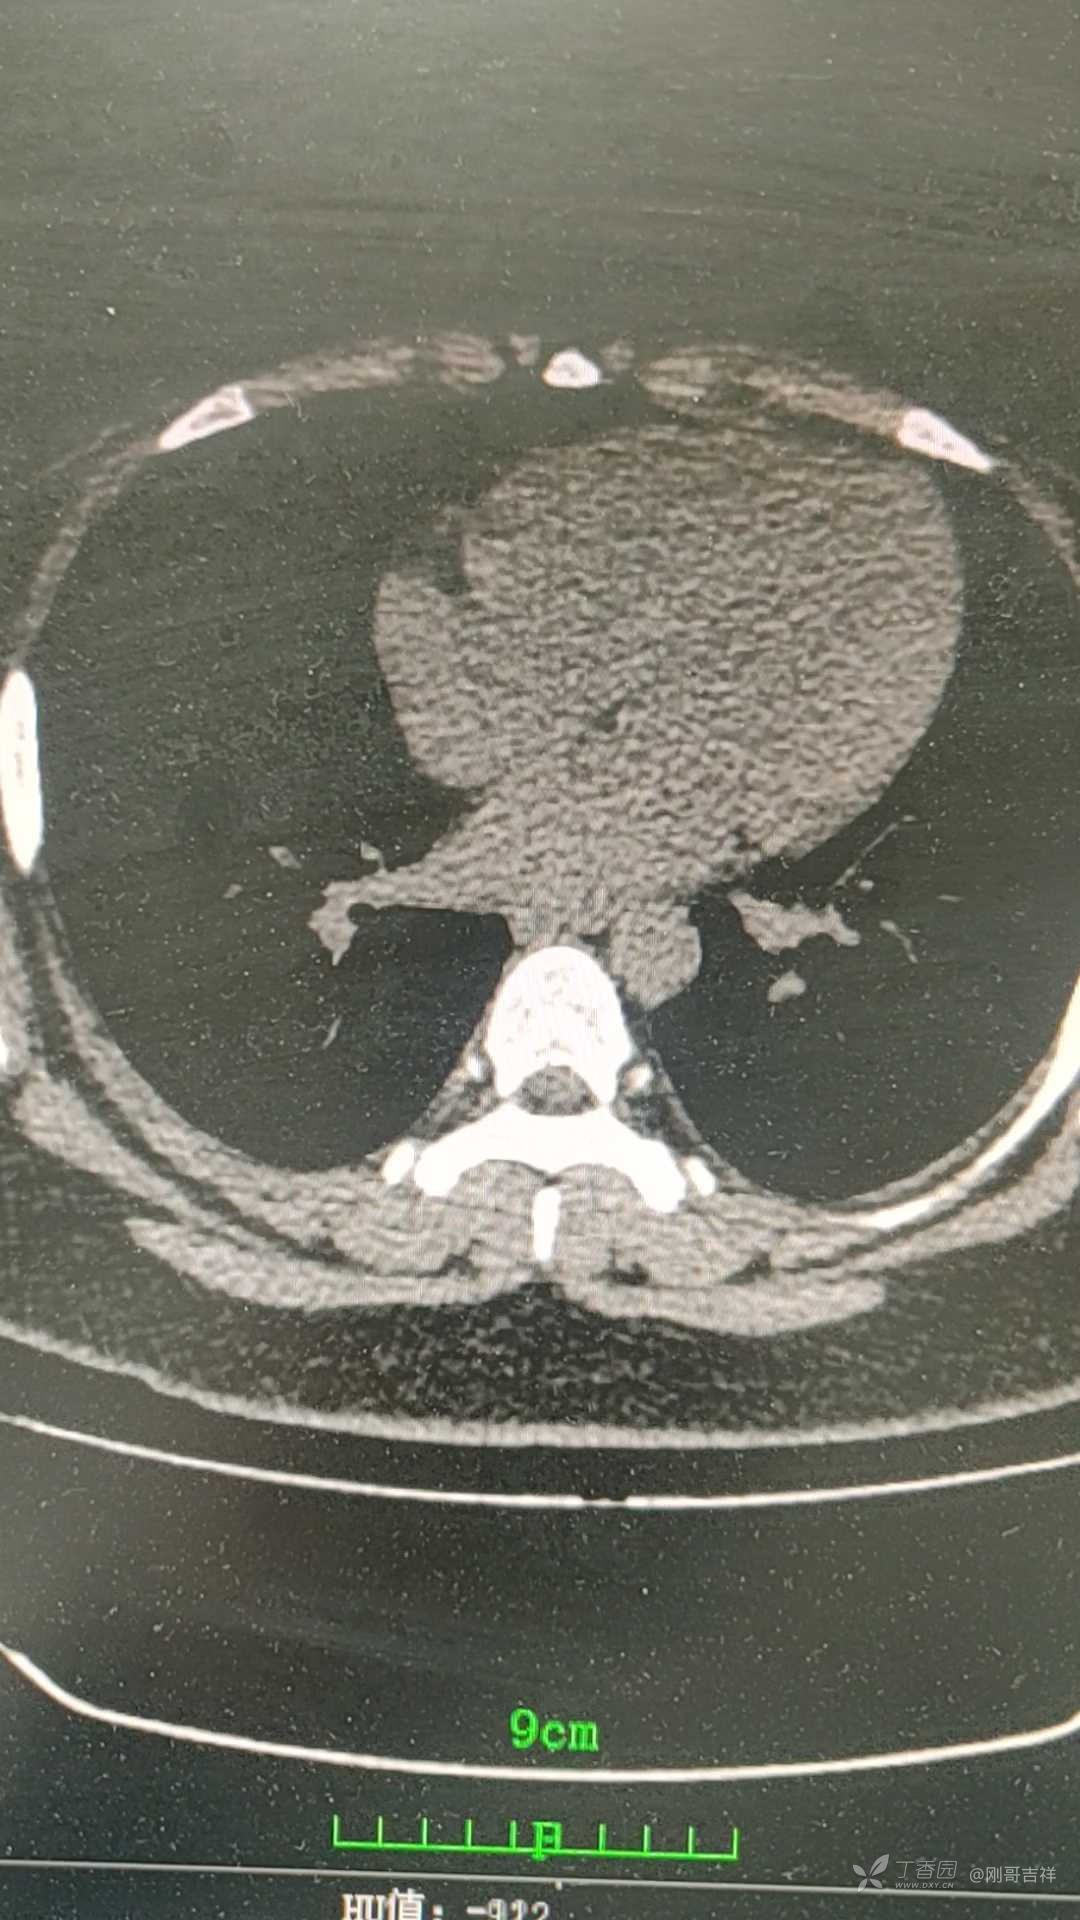

一女性患儿,13岁,体重超重100kg,反复发热近2月,跑遍各大医院,检查未见明显异常,据家长说只等"基因"结果了,家长很焦虑。来我院就诊,查尿常规示白细胞300+cell/ul,肾脏超声示左肾体积增大,做肾脏,腹部加强CT未见明显异常,心脏超声未见异常。泌尿系超声未见异常。反复低热,请教病因?